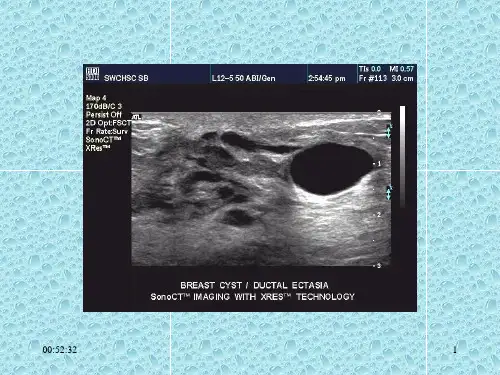

导管乳头状瘤,示导管的扩张及管内实性回声